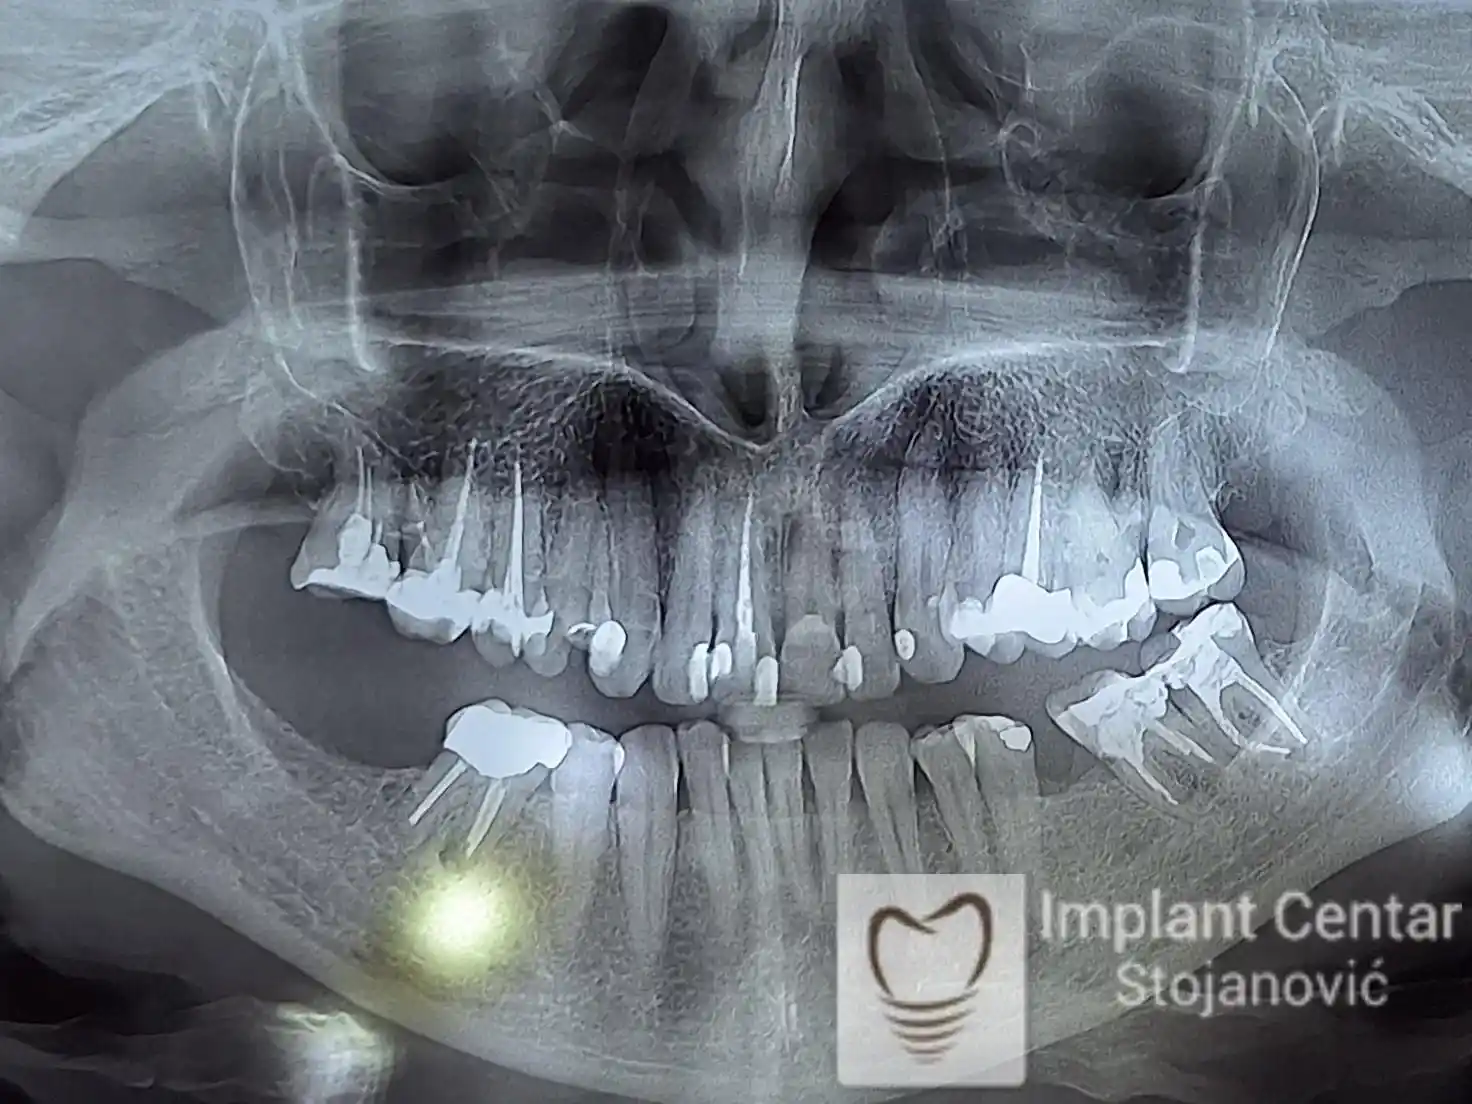

Na slikama 1, 2, 3 , 4  i  5 prikazan je izgled pacijenta pre početka terapije. Nakon detaljne kliničke i radiološke analize, doneta je odluka o vađenju zuba loše biološke vrednosti, dok su bezuba polja sanirana ugradnjom dentalnih implantata.

Nakon ugradnje implantata i pripreme preostalih zuba, pacijentu su izrađene fiksne privremene krunice, čime je postignut eugnatan zagriz već nakon jednog dana (slika 8, 9 i 10). Tokom perioda osteointegracije, pacijent se postepeno privikavao na novi položaj vilica i zagriz.

Po završetku perioda integracije, izrađeni su definitivni cirkonijum-keramički mostovi, čime je postignuta potpuna rekonstrukcija zagriza, kao i značajno poboljšanje estetike i oralne funkcije (slika 12, 13, 14 i 15).